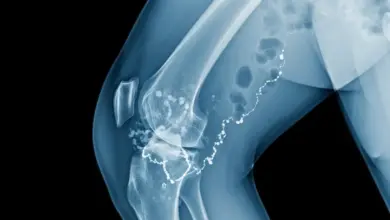

A partir daí se forma a calcificação típica da síndrome de Pellegrini-Stieda, visível na radiografia como uma imagem alongada ou nodular na parte medial do fêmur.

Nas radiografias feitas com o paciente em pé, costuma aparecer a calcificação típica, perto da origem femoral do ligamento colateral medial.